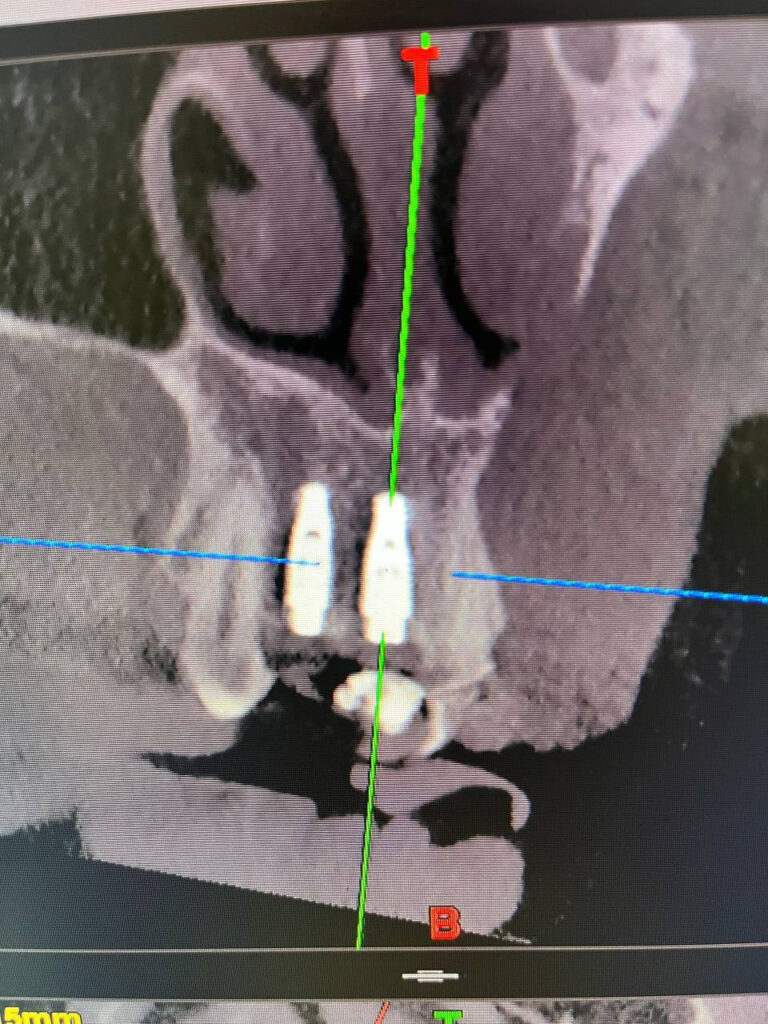

Конусно-лучевая компьютерная томография (КЛКТ) позволяет:

- Видеть кости, нервы, корни и синусы в 3D

- Точно планировать имплантацию

- Находить скрытые проблемы (кисты, воспаления и др.)